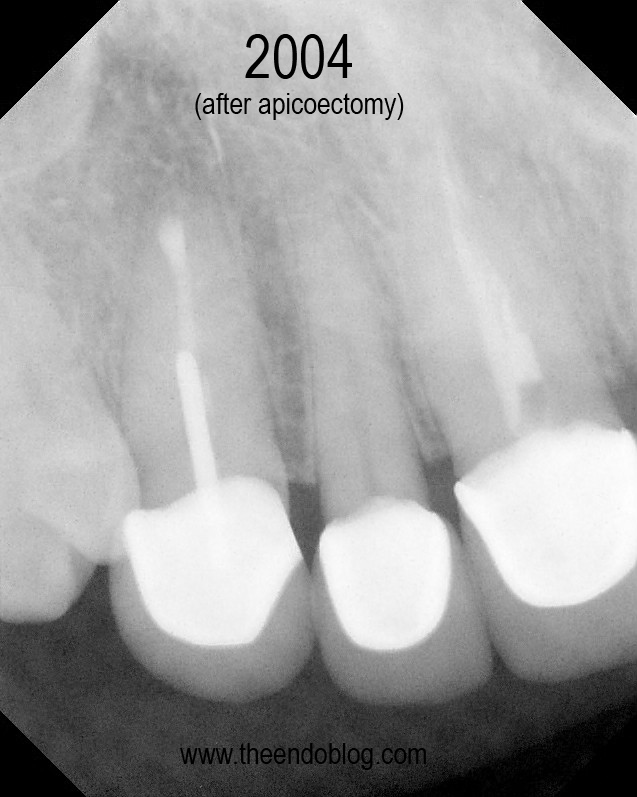

CASE #2

This patient has crowns on #6-#11.  Tooth #6 is causing a localized ache, affected by pressure and chewing. #6 is sensitive to percussion with normal probings. DX:  Prior RCT with Symptomatic Apical Periodontitis (SAP). The margins are suspicious, but apical surgery was chosen to address the infection without disturbing the existing crown.

Apicoectomy completed, no root fractures seen with microscope. MTA retrofill.

9.5 year recall.  Tooth is fully functional, asymptomatic with radiographic healing.  Apicoectomy has preserved the tooth and the periodontium for an extended period of time.